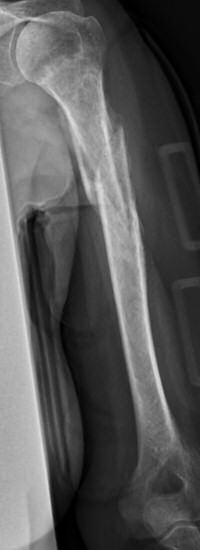

Exempel på humerusfraktur som behandlats icke-kirurgiskt, röntgenbilder efter 19, 40 resp. 71 dagar